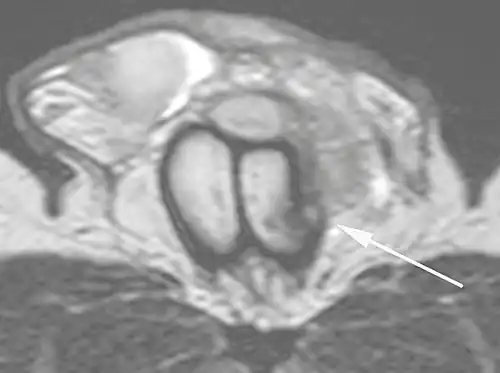

![B: Axial T2-weighted turbo spin-echo magnetic resonance imaging scan showing left-sided discontinuity of the tunica albuginea (arrow), secondary to fracture.[2]](./_assets_/MRI_of_ruptured_tunica_albuginea.jpg) B: Axial T2-weighted turbo spin-echo magnetic resonance imaging scan showing left-sided discontinuity of the tunica albuginea (arrow), secondary to fracture.[2] B: Axial T2-weighted turbo spin-echo magnetic resonance imaging scan showing left-sided discontinuity of the tunica albuginea (arrow), secondary to fracture.[2]

Ultrasound examination is able to depict the tunica albuginea tear in the majority of cases (as a hypoechoic discontinuity in the normally echogenic tunica). In a study on 25 patients, Zare Mehrjardi et al. concluded that ultrasound is unable to find the tear just when it is located at the penile base. In their study magnetic resonance imaging (MRI) accurately diagnosed all of the tears (as a discontinuity in the normally low signal tunica on both T1- and T2-weighted sequences). They concluded that ultrasound should be considered as the initial imaging method, and MRI can be helpful in cases that ultrasound does not depict any tear but clinical suspicions for fracture are still high. In the same study, authors investigated accuracy of ultrasound and MRI for determining the tear location (mapping of fracture) in order to perform a tailored surgical repair. MRI was more accurate than ultrasound for this purpose, but ultrasound mapping was well correlated with surgical results in cases where the tear was clearly visualized on ultrasound exam.[10] The advantage of ultrasound in the diagnosis of penile fracture is unrivaled when its noninvasive, cost-effective, and nonionising nature are considered.[11]